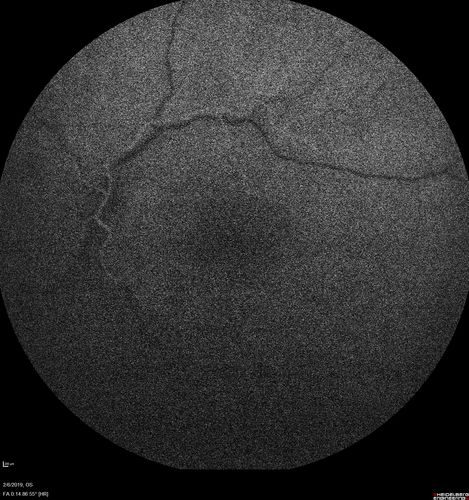

Chronic Endophthalmitis and Cystoid Macular Edema

VA 20/50 - Culture negative. Cleared with intravitreal antibiotics and decadron